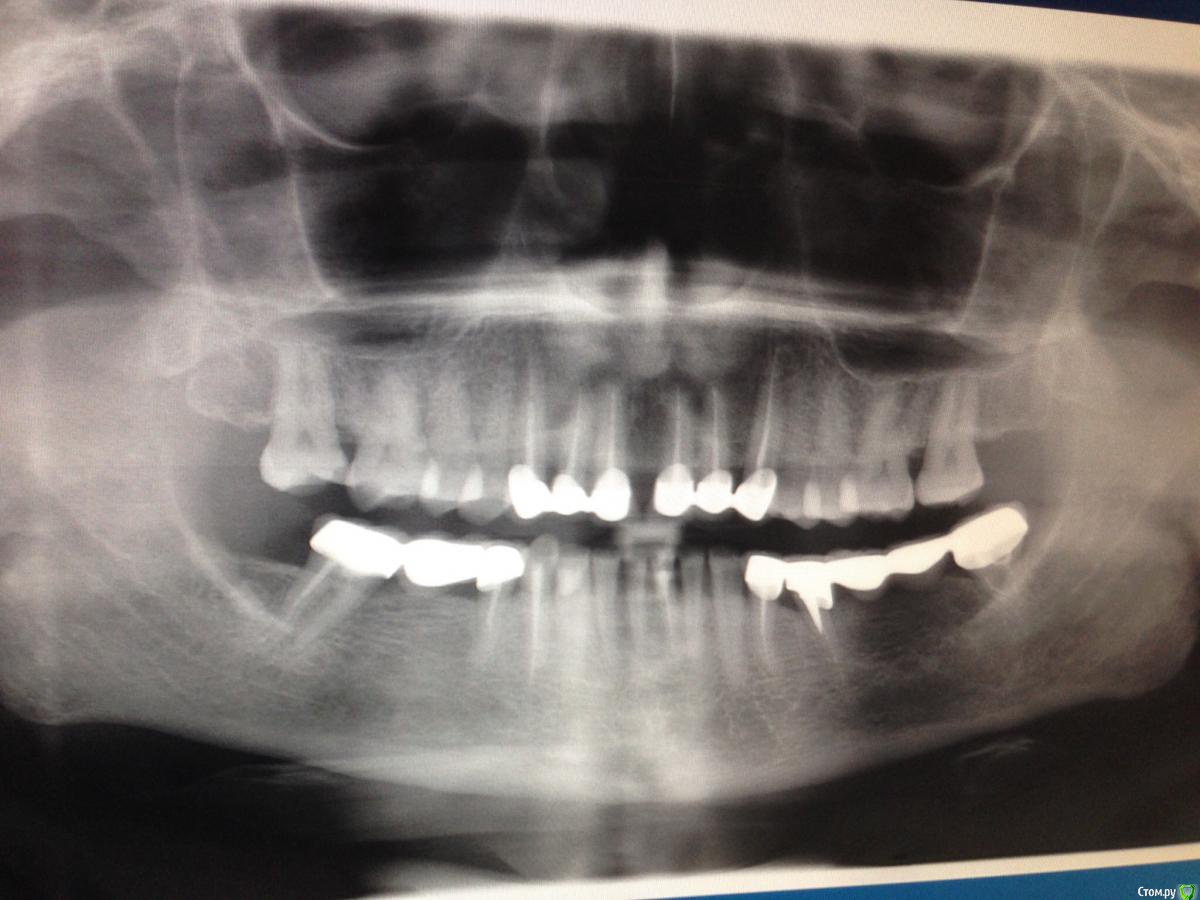

Bratok Опубликовано 27 апреля, 2015 Поделиться Опубликовано 27 апреля, 2015 Позвольте задать вопрос в эту тему дабы не плодить лишних Ситуация на rg.Фронтальные нижние зубы и верхние в боковом отделе значительно истерты, жевательные поверхности плоские, явно снижение высоты. Верхние резцы перекрывают нижние на 2/3.Пациентка хочет заменить старые пломбы..которые вскоре "сотрутся" об керамику. Как бы поступили Вы? Преп всех витальных зубов и покрыть emax коронками? Можно ли отлить диагностические модели и попросить техниа сделать waxup с завышением высоты на 1-2мм после чего "наклеить" этот мокап в рот, предварительно проведя депрограммацию жевательных мышц(15-20 минт с разобщени посидть) Если да то сколько времени понадобится для привыкания? После чего уже по этому waxup будет керамика.Прошу не кидать тухлые помидоры, хотел бы узнать на сколько то, что я написал имеет право на жизнь или это полная чушь? Спасибо!! Ссылка на комментарий

Slaggy Опубликовано 29 апреля, 2015 Поделиться Опубликовано 29 апреля, 2015 Ситуация на rg. По ситуации на снимке - нужно плясать не от имеющейся во рту работы, а от идеального прикуса.Не всегда нужно сохранять то, что у пациента во рту. Тем более, что по снимку есть сомнения в качестве имеющихся конструкций/опорных зубов. Если на старой работе окклюзионная кривая, бугры на молярах, да хоть что-то сделано неверно, с ошибкой, то своей работой, новой конструкцией вы зафиксируете эту ошибку, это патологическое состояние на долгие годы. Ссылка на комментарий